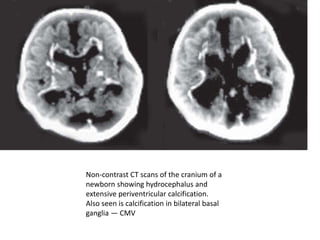

Non-contrast CT scans of the cranium of a

newborn showing hydrocephalus and

extensive periventricular calcification.

Also seen is calcification in bilateral basal

ganglia — CMV